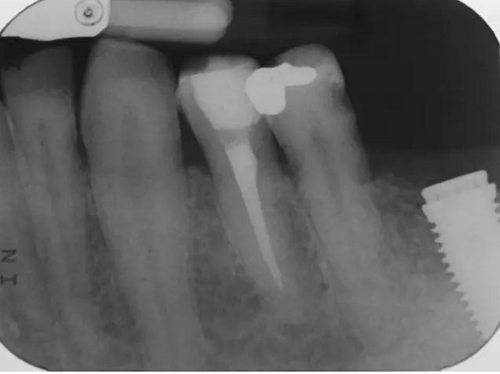

圖4 該病例中,左下4根充失敗,左下5牙髓壞死。兩個(gè)牙齒均需要根管治療和修復(fù)。

圖5 根管治療術(shù)后。左下4需要使用纖維樁,并用雙固化樹脂粘結(jié)劑粘結(jié)。左下5無需纖維樁。但2個(gè)牙齒均需要進(jìn)行覆蓋牙尖的修復(fù)。